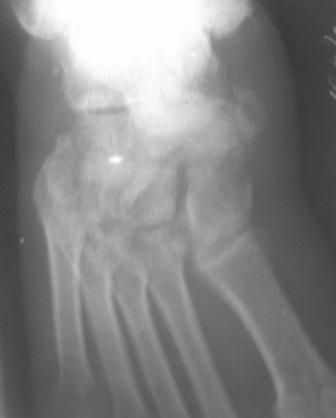

Обратился больной 46 лет. 3 месяца назад получил травму левой стопы в результате ДТП, живет в отдаленный степной зоне, лечился у местного табиба. Ходит при помощи двух костылей, наступая на пятку, на передный отд стопы наступать не может из-за боли, умеренная отечность стопы и деформация в обл. ладьевидной кости, движения в голеностопном суставе в польном обьеме, в средном отд ограничены и болезненны. Уважаемые коллеги, я пока не знаю что делать, помогите, пожалуйста, советами! С уважением Абдурашид.

По данному случаю, оказалось 3 месяца назад было произведена Р-графия в райбольнице, но больной предпочел лечится у табиба. Присылаю первичные снимки.

Да, наш с Вами диагноз, Абдурашид, подтвердился. Я бы предпочёл артродез, фиксация- в самом простом варианте-винтами 3,5 или 4,5 . Отломок послужит аутотрансплантатом. Плюс внешняя иммобилизация. С уважением, Волна